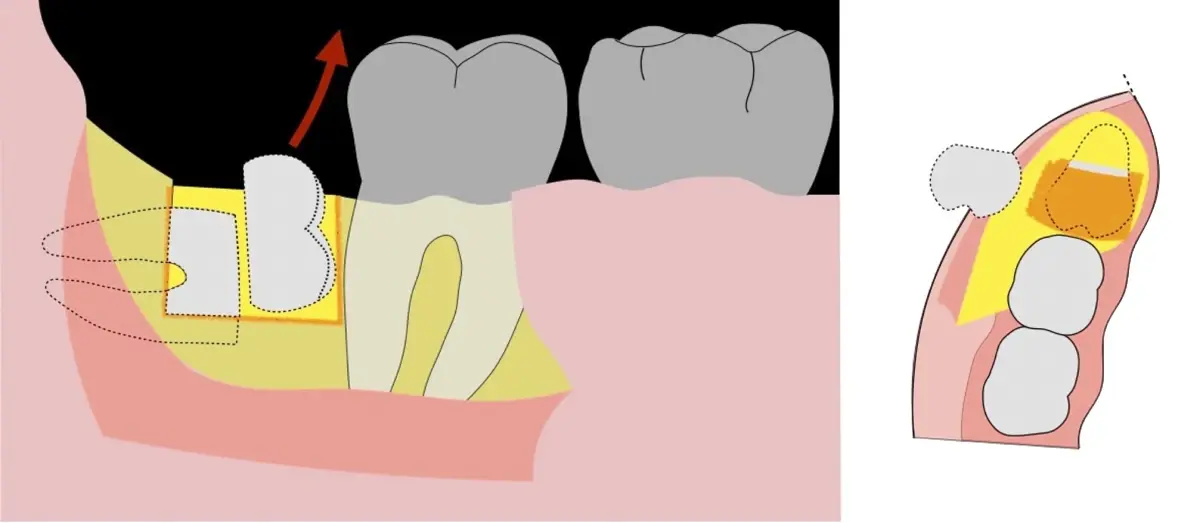

Figura 12. Eliminación del capuchón pericoronario y verificación del lecho óseo posterior a la exodoncia.

Figura 13. Afrontamiento del colgajo y sutura.